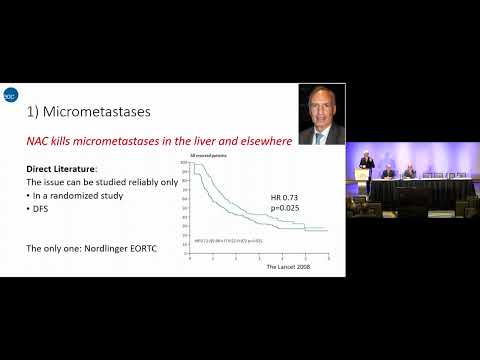

DEB02: Chemotherapy Should Always be Given Prior to Liver Surgery for CRLM? Pro/Con

Debate 02: Chemotherapy Should Always be Given Prior to Liver Surgery for CRLM? Pro/Con